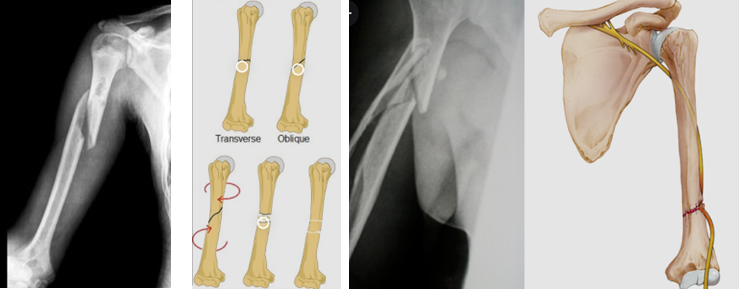

GÃY THÂN XƯƠNG CÁNH TAY

Xương cánh tay có nhiều cơ bám vào, nên khi gãy thường gây di lệch ổ gãy

Thần kinh quay ở sát thân xương cánh tay, nên khi gãy dễ bị mảnh gãy cứa đứt dây thần kinh khiến mất cảm giác và vận động cổ tay

Trên phim Xquang bác sĩ sẽ thấy vị trí của ổ gãy, kiểu gãy ngang hay chéo hay gãy có nhiều mảnh

Tổn thương thần kinh quay: Xảy ra trong 18% số ca gãy xương cánh tay. Khi gặp biến chứng này bệnh nhân sẽ bị liệt thần kinh quay, gây mất duỗi cổ tay. Chiến lược điều trị là mổ xương kèm mổ nối vi phẫu thần kinh quay, cùng với quá trình tập luyện sau mổ, dự kiến sau nối vi phẫu thần kinh sẽ phục hồi sau 12 tháng, đây là thời gian cần thiết để các tế bào thần kinh mọc lại sau khi nối. Ở người trẻ tuổi thì thời gian này có thể ngắn hơn một chút do khả năng phục hồi của người trẻ là rất mãnh liệt.